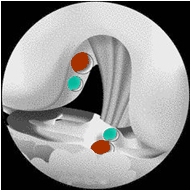

ZE Reconstruction du ligament croisé antérieur "à deux faisceaux"

Cette reconstruction à "deux faisceaux" a pour objectif de se rapprocher davantage de l'anatomie normale du LCA. Ce ligament est en effet constitué en fait de deux faisceaux, intimement liés lors de la flexion du genou :

un faisceau antéro-médial (AM) qui contrôle la translation antérieure du tibia sur le fémur, tendu en extension et en flexion

- un faisceau postéro-latéral (PL) qui contrôle la rotation, et en particulier le ressaut en rotation interne, qui se détend lors de la flexion du genou.

Lors du forage des tunnels, ceux-ci sont réalisés distinctement, 2 tunnels dans le tibia et 2 dans le fémur

Les transplants (DI pour le faisceau PL et DT pour le faisceau AM) sont ensuite passés en 2 temps puis fixés au fémur et au tibia

Les indications de cette technique à deux faisceaux dépendent de la nature de la rupture du LCA, de l'importance de l'instabilité et des habitudes du chirurgien. Elle n'a cependant pas fait la preuve de sa supériorité par rapport à la technique classique "mono-faisceau".